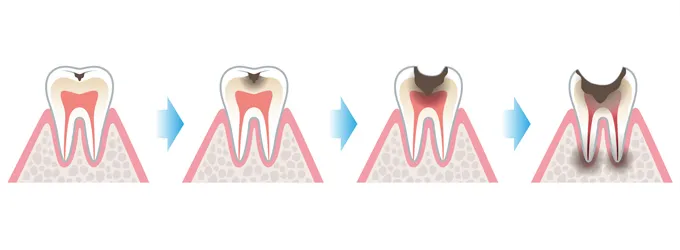

虫歯治療の場合、酸で溶かされて弱くなった部分を削って、詰め物や被せ物などで空いてしまった穴を塞ぐという治療を行います。しかし、しっかりと穴を埋めてくれた被せ物や詰め物にも寿命があるのです。

虫歯の進行を留めてくれていた被せ物や詰め物も時間が経つと、被せ物・詰め物が歯にしっかり密着できなくなり、歯との間に隙間ができてしまいます。すると、虫歯治療で削った部分に歯垢が入り、虫歯菌が繁殖してどんどん虫歯が進行していきます。

虫歯の上に被せ物や詰め物があるため虫歯の進行に気が付きにくいこと、また大人になると神経に至るまで痛みが出にくいという点も、虫歯をかなり進行させてしまう原因になります。

歯髄と呼ばれる神経や血管があるところまで虫歯が進行すると、顎の骨の部分が腫れてしまうなど、大事になる場合もあります。定期的に歯科医院に通って、歯ブラシなどで落としきれない歯垢をしっかり落としてもらいましょう。